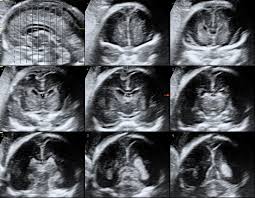

Fetal neurosonogram

Fetal neurosonogram (also called fetal neurosonography) is a detailed ultrasound scan of a baby’s brain and spinal cord performed during pregnancy. It provides in-depth imaging of the fetal central nervous system (CNS) — primarily the brain and upper spine — to detect abnormalities or monitor development.